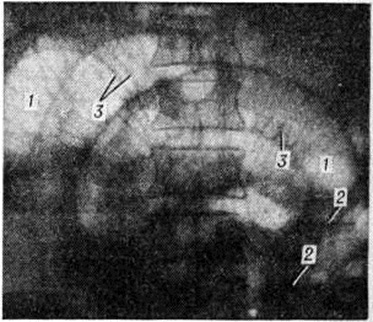

Рис. 1.

Макропрепарат резецированного отдела тонкой кишки при странгуляционной непроходимости, возникшей при спаечной болезни: 1 — странгуляционная борозда на границе с отводящим отделом; 2 — ущемлённый отдел кишки; 3 — странгуляционная борозда на границе с приводящим отделом; 4 — приводящий отдел.